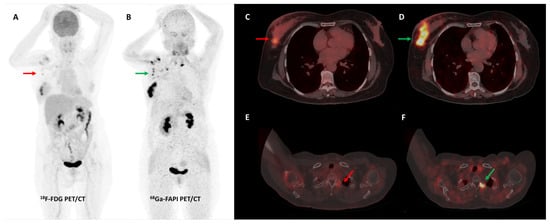

Breast cancer is characterized by a remarkable degree of genetic and molecular heterogeneity. Differences in receptor status expression are fundamental to the biological behavior of breast cancer subtypes, directly impacting imaging and treatment strategies [105]. In recent years, radiotracers specific to the estrogen receptor (ER) and human epidermal growth factor receptor 2 (HER2) such as [18F]fluoroestradiol (FES) and [89Zr]Zr-Trastuzumab, respectively, have demonstrated clinical utility [106,107]. FAP targeting represents a promising approach to indirectly assess tumor burden as CAFs are the most abundant cells in the breast cancer microenvironment. Komek et al. conducted a pilot study, prospectively comparing [68Ga]Ga-FAPI-04 and FDG PET/CT in 20 women with histopathologically confirmed breast cancer. FAPI had higher sensitivity (100% vs. 78.2%) than FDG PET/CT, with comparable specificity (96.5% vs. 100%) for the detection of primary breast lesions. The SUVmax values of primary breast lesions, lymph nodal, lung, and bone metastases were significantly higher with FAPI than FDG (p < 0.05) [108]. Figure 6 shows a representative example.

Figure 6.

[68Ga]Ga-FAPI-04 performed better than FDG PET/CT for initial staging in a 51-year-old woman with histopathologically proven triple receptor-negative invasive breast cancer. FDG PET/CT (A) revealed mildly tracer avid right breast primary ((C)—red arrow) with few faintly FDG avid right axillary lymph nodes ((A)—red arrow). FAPI PET/CT (B) demonstrated intensely tracer avid right breast primary ((D)—green arrow), multiple right axillary lymph nodes ((B)—green arrows), and few lytic skeletal lesions such as one involving the left transverse process of C2 vertebra ((F)—green arrow), which showed no abnormal FDG uptake ((E)—red arrow).